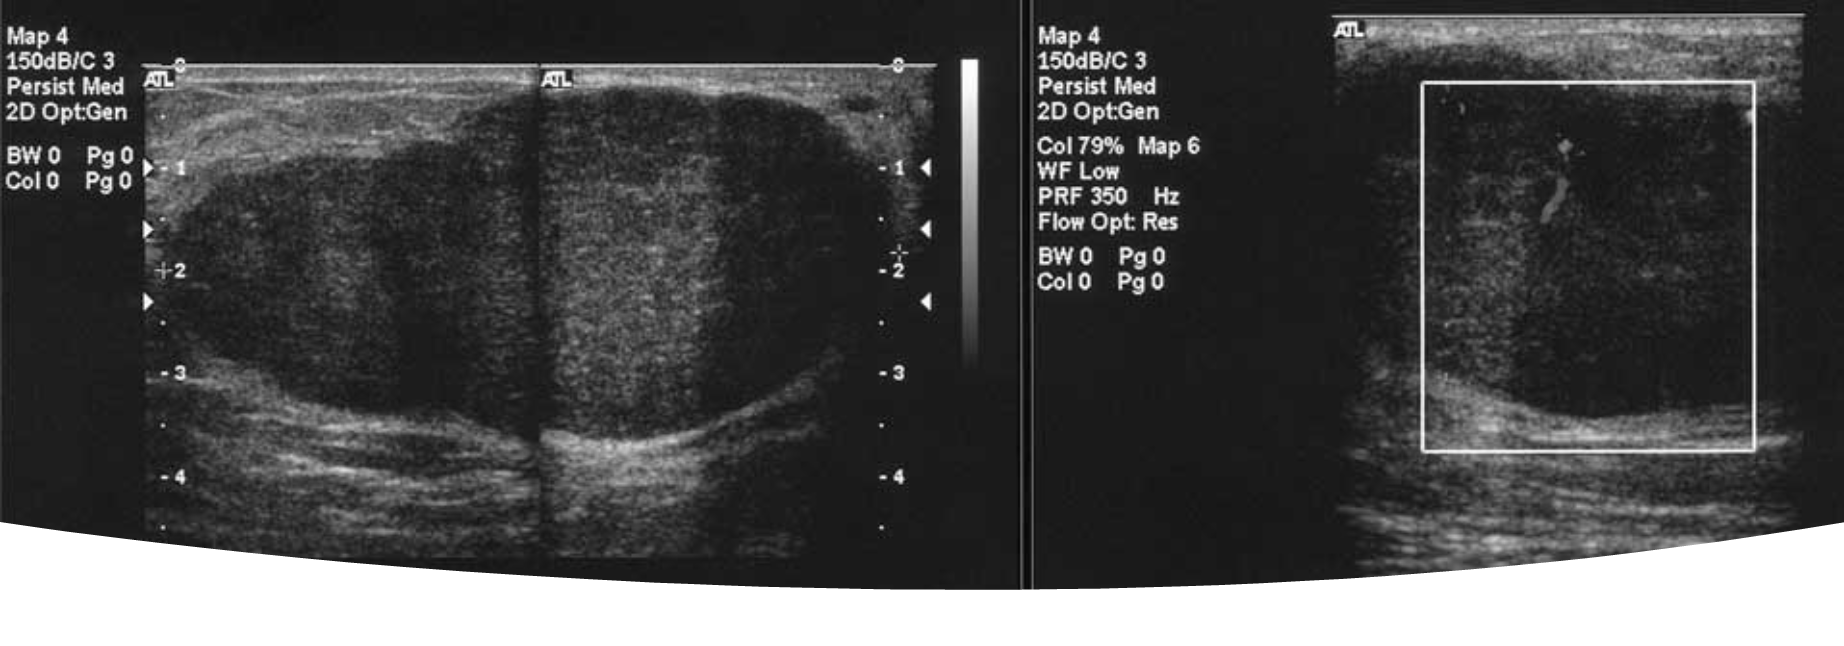

What are theses images showing?

fibroadenoma on ultrasound

What is this image showing?

a giant fibroadenoma/juvenile fibroadenoma